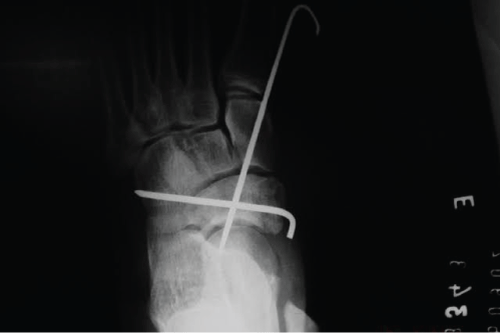

The K-wires maintained for 7 weeks after the first surgery, together with the use of a plaster boot. Patient, then, had the wires removed (Figure 3), referred to physiotherapy and had total load liberated 7 weeks after the wire removal. Patient developed a complete recovery from foot range of motion and discharged asymptomatically.

About five months after the initial injury, the patient had a medical appointment again, due to pain and edema in the left tarsus, especially in the late afternoon, after normal work routine that involved intense walks in high heels. Radiography performed, it showed signs of chondrolysis (Figure 4)-a complication also described in the literature, which is cartilage degeneration with reduced blood supply, causing avascular necrosis of this structure and subluxation of the navicular [2]. CT scan performed, which confirmed the chondrolysis with degenerative changes in the talusnavicular and cuneiform joints. Because of this injury, the patient was submitted to selective arthrodesis with in situ fusion of the left tarsus [8] (Figure 5) - procedure performed to cause bone fusion in a joint, thereby causing immobility-with three cannulated cancellous screws of 4.5 mm, with very satisfactory final result. The open reduction internal fixation done through dorsomedial surgical access over the navicular with arthrodesis of talus navicular and cuneiform medial-talus-navicular (TN+CTN). Postoperatively the plaster boot used for 9 weeks. Subsequently, the X-ray showed consolidated arthrodesis, and the patient liberated to ambulation with hard shoes for another 60 days. About a year later, the removal of the screws done.

Figure 4: X-ray showing chondrolysis in talusnavicular and navicular cuneiform joints.